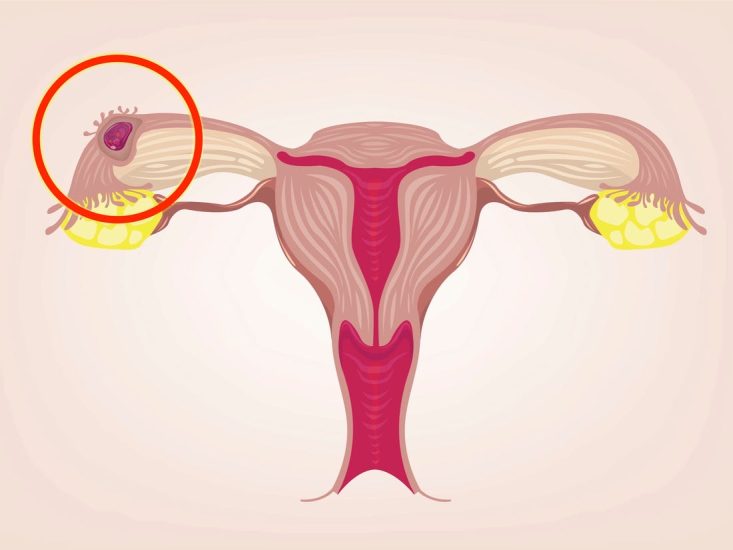

Një shtatzëni ektopike ndodh kur një vezë e fekonduar implantohet në vendin e gabuar në trupin e një gruaje. Pra, në vend që të ngjitet në mukozën e mitrës, ku mund të mbijetojë, ajo rritet diku tjetër.

Më shumë se 90 për qind të rasteve, në një shtatzëni ektopike, veza e fekonduar implantohet në një nga tubat fallopiane të një gruaje, të cilat lidhin vezoret me mitrën.

Tubat fallopiane janë të hollë dhe plot enë gjaku. Nëse ato shpërthejnë, siç mund të ndodhë kur një vezë e fekonduar rritet në tub, kjo mund të shkaktojë gjakderdhje të brendshme.

Në raste të rralla, një shtatzëni ektopike mund të implantohet diku tjetër, si në vezore, qafën e mitrës apo edhe një pjesë të brendshme të prerjes cezariane.